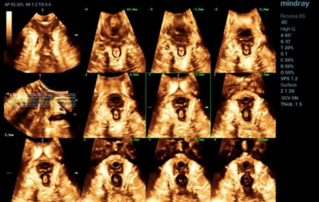

Endocavity ?? ?? ?? ???(DE10-3WU, Resona 7, Mindray)? ??? ??? ???? ?? ?? ????(Levator ani nuscle)? ??? ???. ???? ?? ??? 3~4mm? ????, ???(levator hiatus) ?? ?? - 6.13cm, LUG1(??? m ??? ??. Bulbocavernosus) ŌĆō 2.95cm ? LUG2 ŌĆō 3.15cm(?? 2.5cm ??)

??????? ??? ?? ? ??? ??? ??? ?????, ?? ??(pelvic floor) ??? ??? ?? ??(??? ?/?? ??)? ??? ???. ? ?? ???? PVA, RVA ? PUA ?? 20┬░ ???? ?????. ? ?? ???? PVA ŌĆō 134o, RVA ŌĆō 82o ? PUA ŌĆō 119o.

??? ???? ??? ?? ????? ??? ??? ?? ?????. ????? ? ??? 30mm?? 42mm?? ??? ? ??? ??? ??? ????? ?? ? ? ?? ? ?? ? ?? ??? ??? ??? ? ????. ?? R ? ???? ?? ?? ?? ?? ?? 7mm, ?? ?? 8mm???.

?? ? ???????? ?? ?? ??? ??? ???? ???? ?? ?? ??? ????. ????? ?????? ???? CUDI(??? ???? ??) ? ??? ??? ???? ? ??? ??? ? ?? ???, CUDI, ???(pessary)? ??? ?? ???(???? ??? ???? ? ? 7? ??). ?? ??? 3D ??? ? ?? ??? ??? ??? ?? ??? ?? ???? ??? ?? ?? ??? ????? ???? ?? ??? ??? ??? ????.